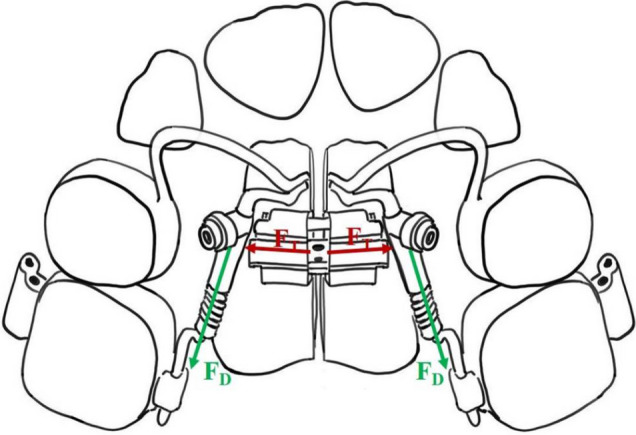

恒前牙的延迟出牙,伴随着牙弓空间不足,是混合牙列的重要挑战。本研究的目的是评估一种改良的正畸矫治器的有效性,该矫治器结合了上颌横向扩张和上颌中远端延伸,并控制恒磨牙的远端,用于治疗混合牙列期间前牙延迟萌出的病例。本研究包括前瞻性比较设计,研究组35例患者和对照组32例患者,均表现出恒前牙延迟萌出的临床和放射学征象。研究组接受改良的正畸矫治器的治疗,旨在同时实现上颌扩张和磨牙远端。对照组采用Haas矫治器进行上颌扩张,远端喷射器进行磨牙远端拔除。使用统计检验确定显著性水平,计算关键结果的p值。研究显示,改良的正畸矫治器与对照组相比,显著减少了在牙弓内创造足够空间所需的治疗时间(p = 0.017)。研究组并发症发生率为17.14%,低于对照组28.12%,差异有统计学意义(p = 0.046)。研究组患者的积极感知率(68.57%)高于对照组(43.75%),差异有统计学意义(p = 0.031)。两组间磨牙远端和上颌扩张量差异无统计学意义(p < 0.05)。一种重新设计的正畸矫治器,结合了上颌横向扩张和磨牙远端,减少了治疗时间和延迟恒前牙萌出的困难。这些数据表明,该器具在不减少空间调整的情况下提高了治疗效率和患者舒适度。它的混合牙列使用需要更多的研究与更大的样本量和规范的处理技术。

Delayed permanent anterior teeth eruption, accompanied by insufficient space in the dental arch, presents a significant challenge during mixed dentition. The aim of this study was to assess the effectiveness of a modified orthodontic appliance that combines transverse maxillary expansion and mesio-distal maxillary elongation, with controlled distalization of permanent molars, in treating cases of delayed anterior teeth eruption during the mixed dentition period. The present study included a prospective comparative design, with a study group of 35 patients and a control group of 32 patients, all demonstrating clinical and radiological signs of delayed permanent anterior teeth eruption. The study group received treatment with a modified orthodontic appliance designed to achieve both maxillary expansion and molar distalization simultaneously. The control group was treated with the Haas appliance for maxillary expansion and the Distal Jet for molar distalization. The level of significance was determined using statistical tests, with p-values calculated for key outcomes. The study revealed that the modified orthodontic appliance significantly reduced the treatment time required for adequate space creation within the dental arch compared to the control group (p = 0.017). The rate of complications in the study group was lower (17.14%) compared to the control group (28.12%), with a significant difference (p = 0.046). Patients in the study group also reported a higher rate of positive perception (68.57%) compared to the control group (43.75%), with a statistically significant difference (p = 0.031). No significant difference was found in the amount of molar distalization and maxillary expansion between the two groups (p > 0.05). A redesigned orthodontic appliance that combines transverse maxillary expansion and molar distalization reduces treatment time and difficulties in delayed permanent anterior teeth eruption. These data indicate that the appliance improves treatment efficiency and patient comfort without reducing spatial adjustments. Its mixed dentition use needs more research with larger sample sizes and regulated treatment techniques.